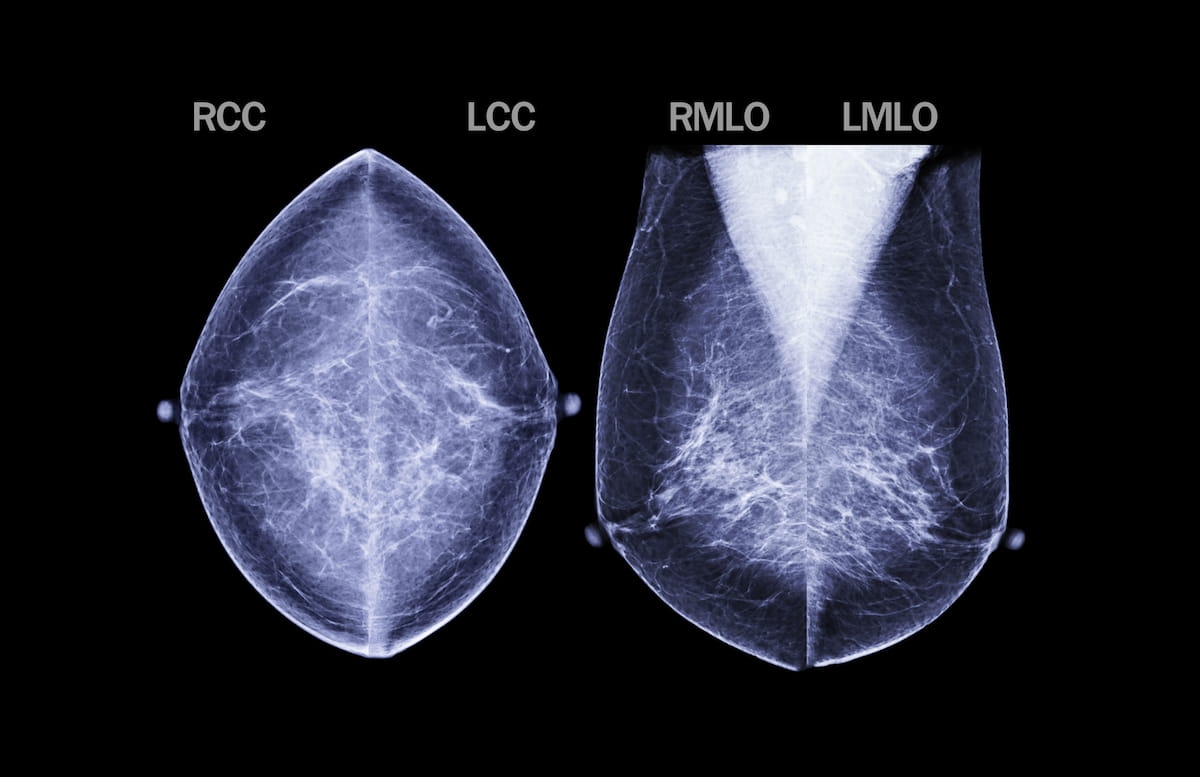

In a review of the literature, this author discusses the viability of artificial intelligence (AI), parallel imaging, compressed sensing and simultaneous multi-slice excitation for improving the scan times and use of magnetic resonance imaging (MRI) to facilitate CyberKnife treatment.